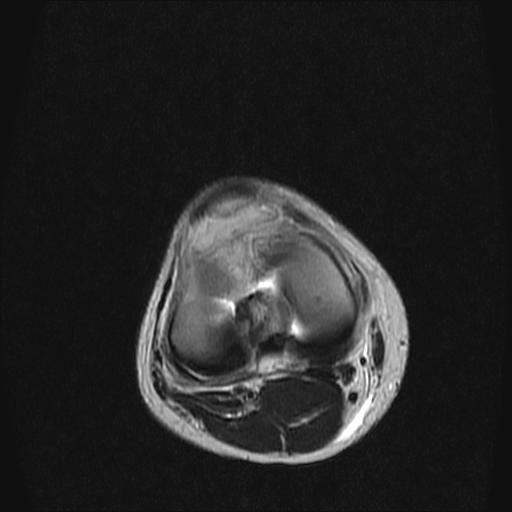

标题: MRI1265:男性40岁,右膝关节 [打印本页]

标题: MRI1265:男性40岁,右膝关节

40岁男性,右膝关节外伤,x光平片示,髁间隆突撕脱骨折。

1、前交叉韧带撕裂;

2、外侧半月板后角撕裂;

3、关节腔积液。

半月板1-2级损伤   前交叉韧带撕裂伤   关节腔少量积液  诸骨未见新鲜外伤性改变

髁间隆突撕脱骨折;内侧副韧带损伤。

除了关节积液外并无韧带撕裂,acl胫侧附着点有2束,正常情况下脂肪信号。此病例应加做压脂像以便观察是否有骨损伤。